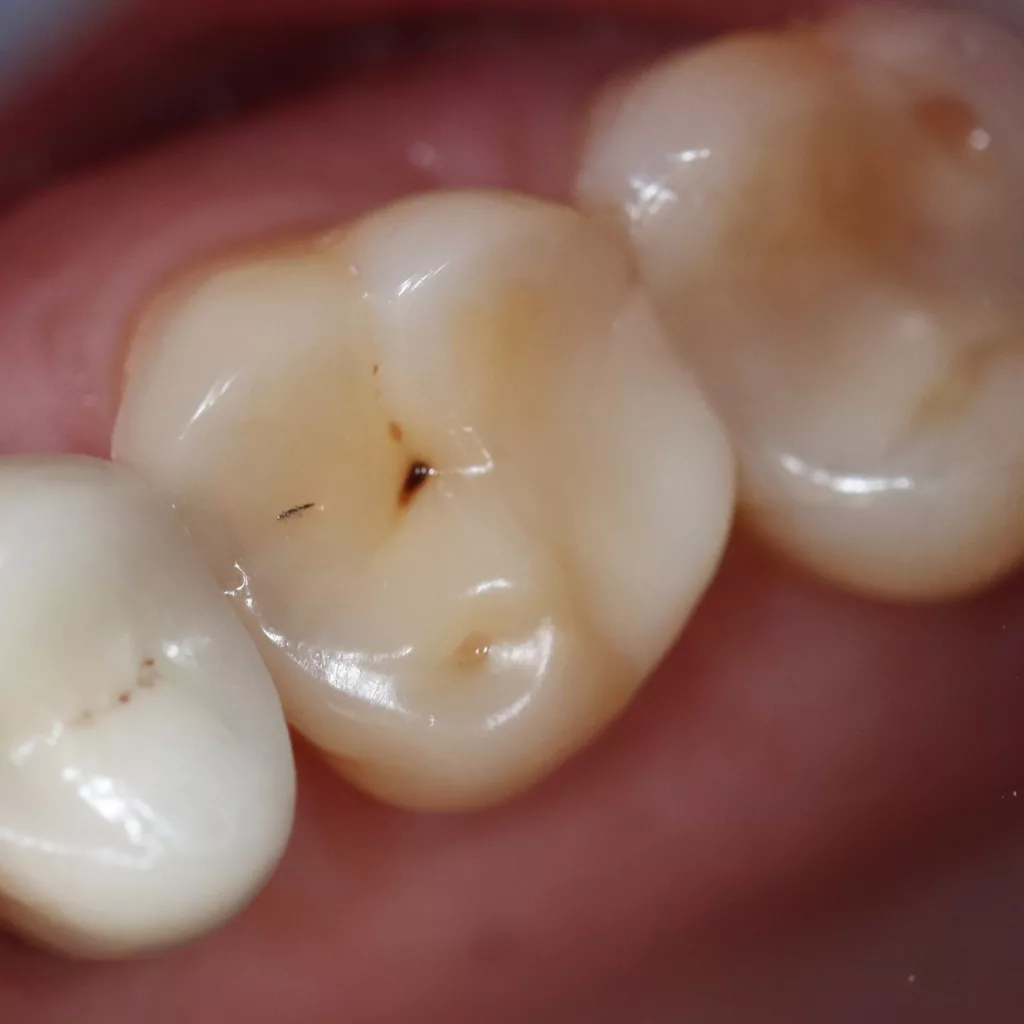

Wird eine profunde kariöse Läsion behandelt, empfiehlt sich folgendes Vorgehen [5]: Zunächst sollte in einem ersten Schritt ein Kofferdam appliziert werden, um eine möglichst keimfreie Arbeitsweise zu gewährleisten. Nach Präparation einer Zugangskavität, wenn dies notwendig ist, erfolgt die Kariesexkavation mittels Rosenbohrern oder Handexkavatoren. Wird in pulpanahen Arealen eine Eröffnung der Pulpa erwartet, sollte das Instrument gewechselt und ein sauberer Rosenbohrer genutzt werden. Tritt nach vollständiger Kariesexkavation keine Eröffnung der Pulpa ein, ist aber von einer dünnen Restdentindicke von etwa 300 µm auszugehen, oftmals erkenntlich durch eine zartrosa hindurchschimmernde Pulpa, sollte nach Kavitätentoilette mittels Natriumhypochlorit (NaOCl) 3% eine indirekte Überkappung mit einem hydraulischen Kalziumsilikatzement erfolgen [5]. NaOCl dient dazu, Bakterien und Toxine zu neutralisieren und das Dentin zu desinfizieren. Die Unterfüllung aus Kalziumsilikatzement soll auch desinfizierend wirken, das Pulpagewebe zur Heilung anregen und vor möglicherweise durch das Dentin penetrierenden Monomeren aus dem Dentinadhäsivsystem schützen [5], da diese die regelrechte Funktion der Odontoblasten beeinträchtigen können [9,40]. Im Anschluss muss eine direkte, dentinadhäsive Restauration zur Versorgung der Kavität platziert werden [5]. Die Abbildungen 1 bis 14 illustrieren das Vorgehen bei der Behandlung einer profunden kariösen Läsion mit indirekter Überkappung der Pulpa.